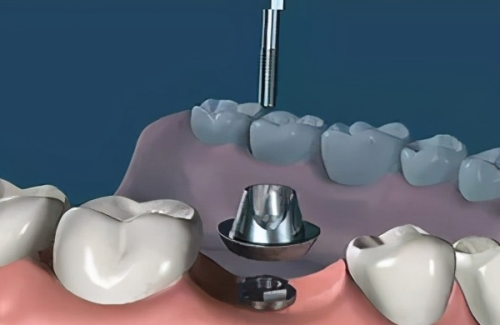

活动义齿一般多少钱一颗费用?2026年最新价格揭秘! 文章揭秘2026年活动义齿最新价格。通常镶活动假牙一颗1000 - 3000元,不同类型费用有别。如隐形义齿1000 - 1200元,便宜但寿命短、咀嚼差;钴铬合金等1500 - 2000元,强度好、使用久;纯钛基托2000 - 3000元,舒适美观。此外,地区、医院等级和医生水平也影响价格,选义齿要综合考量。 活动义齿 2026年03月04日 0 点赞 0 评论 7 浏览

活动义齿哪种最舒服还不伤害基牙?揭秘3种最佳选择! 本文围绕“活动义齿哪种最舒服还不伤害基牙”展开。首先强调了活动义齿舒适与护基牙的重要性,接着介绍了纯钛金属基托活动义齿等三种义齿的特点,包括舒适度、对基牙的影响、价格等。还给出选择建议,要考虑口腔状况、经济因素,并听取医生建议。最后提醒佩戴后注意适应期、清洁和饮食,综合考量选适合自己的义齿。 活动义齿 2026年03月04日 0 点赞 0 评论 12 浏览

补一颗活动义齿多少钱?揭秘真实费用与选择技巧! 本文围绕补一颗活动义齿的费用及选择技巧展开。费用大致在100 - 300元,受材料、修复难易、医院级别、当地经济等因素影响。不同材料义齿各有特点和价格区间。选择时要综合自身情况,选正规机构,多对比。此外,后期维护有成本,需正确佩戴清洁。提醒大家综合考量价格、质量和舒适度,必要时咨询医生。 活动义齿 2026年03月04日 0 点赞 0 评论 7 浏览